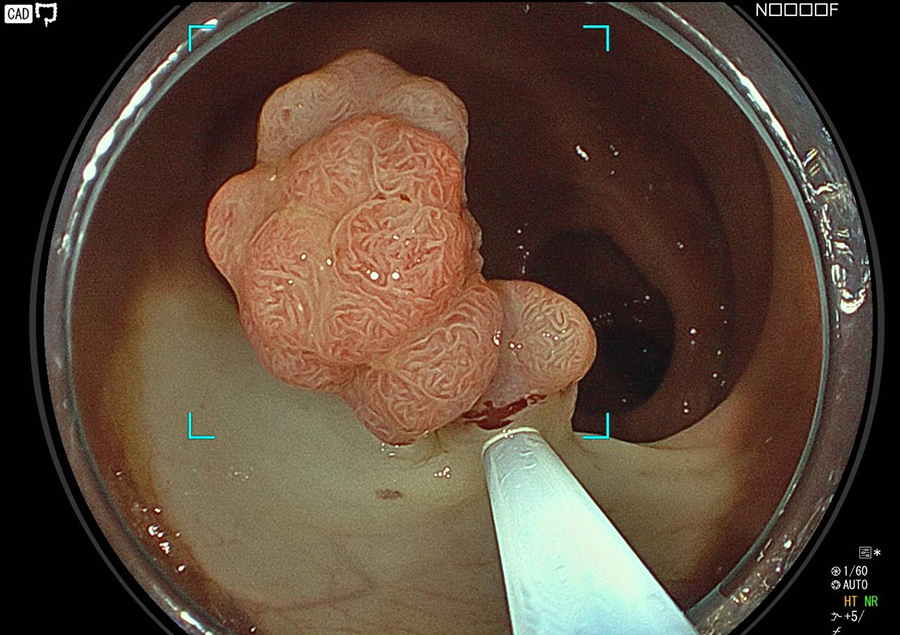

検査の様子

そこで当院では大腸カメラ検査時にポリープや早期がんが発見された場合は、可能な限り積極的にその場で切除しております。

※観察に時間を要する場合や、組織採取・ポリープ切除を行う場合は、検査時間が延長します。

一般的に大腸ポリープのうち、約5%が早期がんといわれ、また良性のポリープもがんの発生母地になるといわれています。